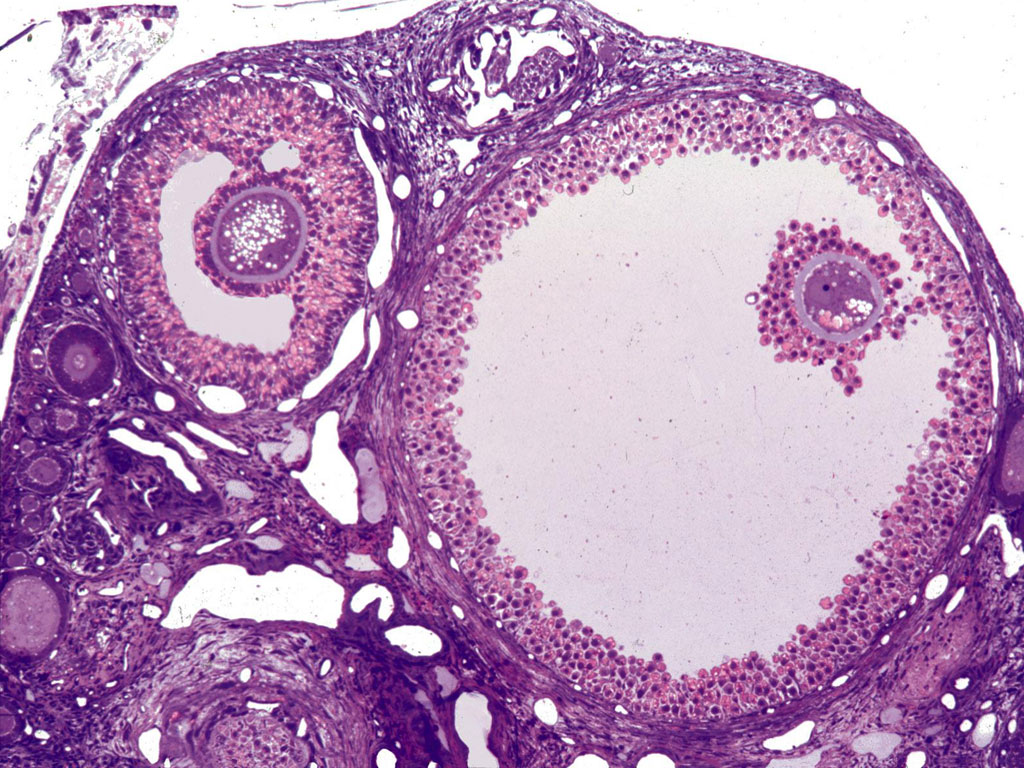

Graafian follicles in ovaries (cow)

What is the large, light pink circular blob on the right side?

What is the clear portion within the ring points 1-5 are called?

Cow oocyte - cytoplasm